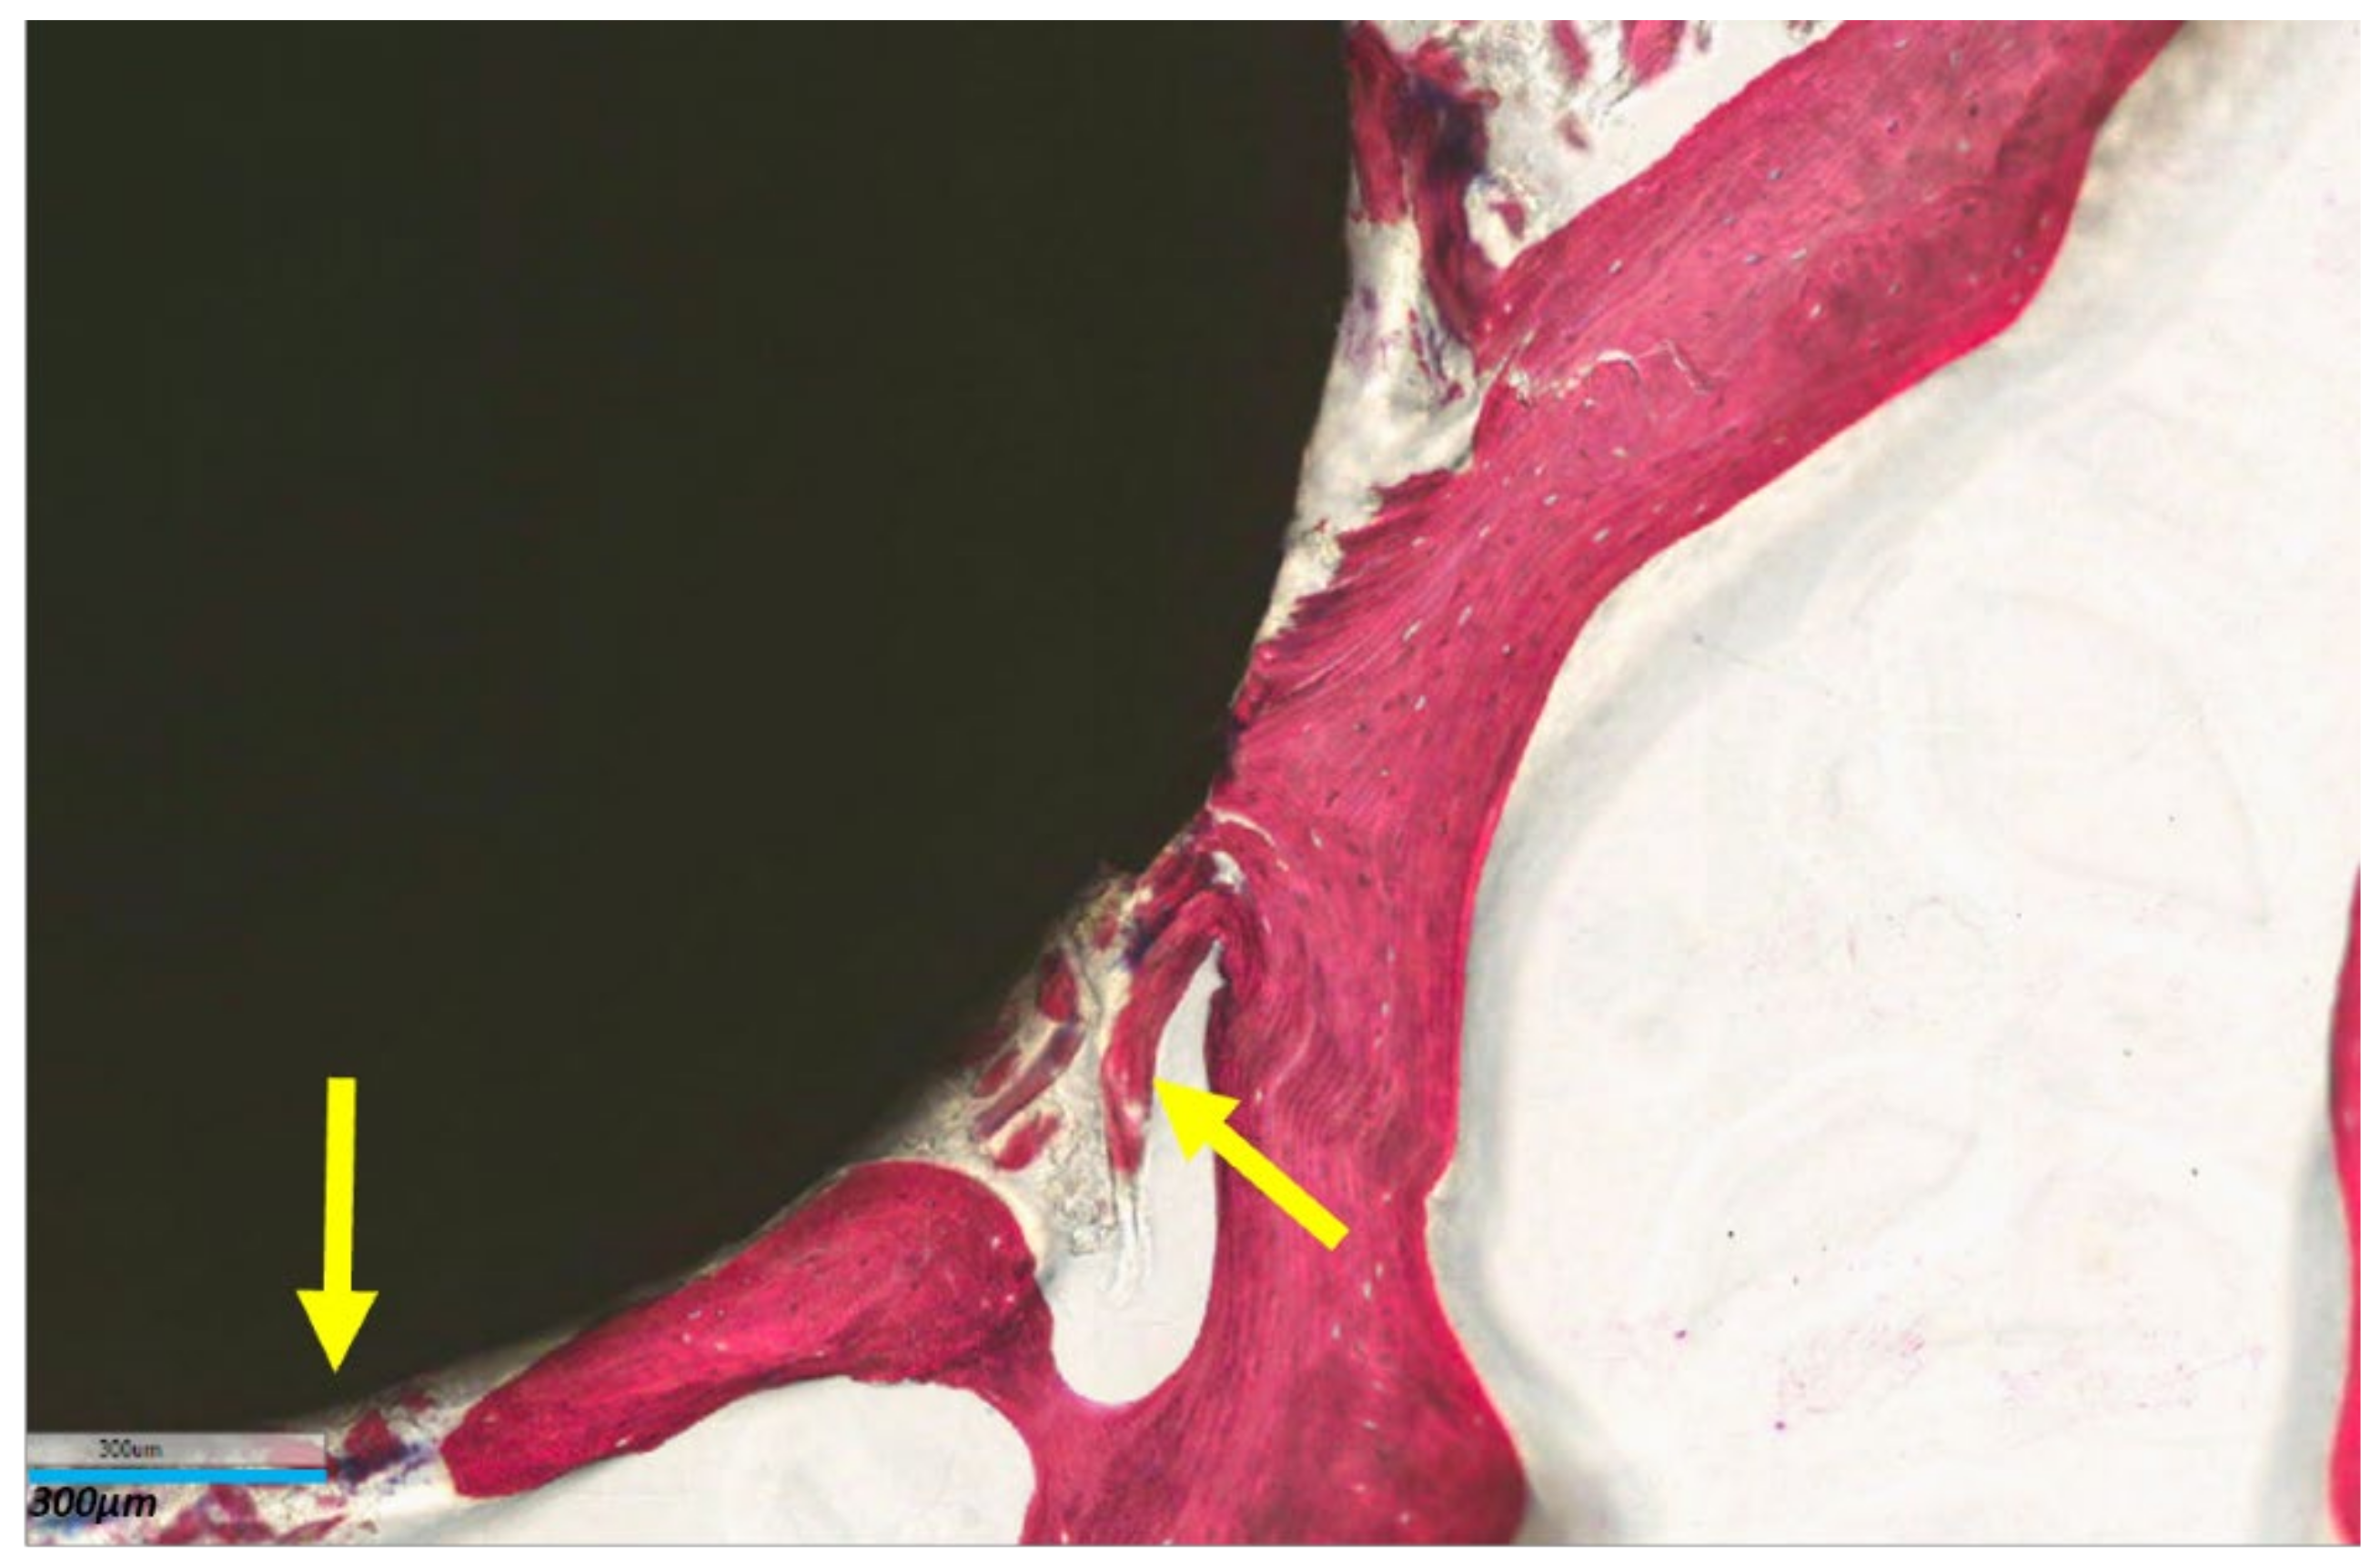

Histomorphometric measurements of BIC at the time of implantation and after 8 weeks of dynamic culture are reported in Table 2. Titanium implants induced a significant increase in the bone-to-implant contact after 8 weeks of culture (p = 0.006) in comparison with the copper cytotoxic material implanted in the trabecular bone. Similarly, histological images at higher magnification evidenced that the in vitro culture of titanium alloy materials not only maintained the bone tissue sample as viable but also induced bone tissue deposition around the implant (Figure 7).

Figure 7. Histological image of trabecular bone tissue sample implanted with Ti alloy at end of 8 weeks of culture (T8). Yellow arrows indicate deposition of new bone tissue trabeculae. Stevenel Blue–Acid Picrofucsin stain, 8× magnification, bar = 300 µm.